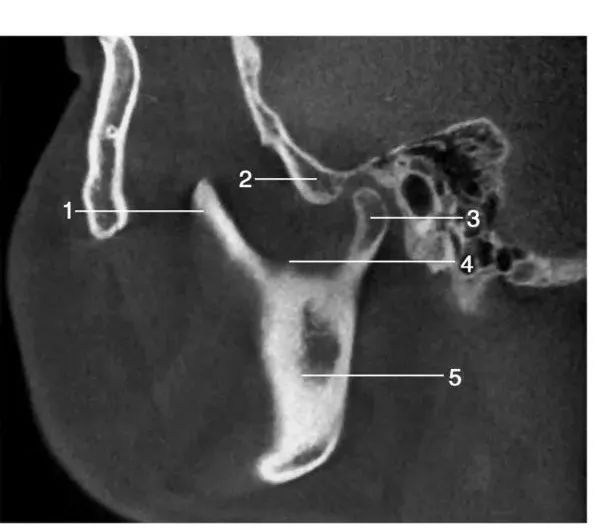

2、矢状位影像经髁突中份层面矢状位图像1.喙突; 2.关节结节; 3.髁突; 4.乙状切迹 ; 5.下颌升支